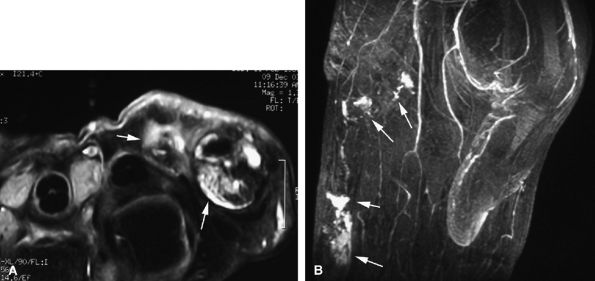

Nodular or tubular enhancement may be seen after gadolinium administration. MRA is complementary to standard MR studies, providing precise details of the angiographic appearance of the malformation (Fig. 11.78). MRA of the fingers is technically challenging because of the small caliber of blood vessels and their changing orientation. The MRA technique that is most suited to the fingers is a 3D coronal acquisition after gadolinium administration. This rapid technique (requiring less than 30 seconds for acquisition) yields high spatial resolution and is not dependent on vessel orientation. Injection of a gadolinium test dose allows precise determination of maximum arterial enhancement.180 Temporal resolution remains inferior to DSA.4

better angiographic assessment of the venous malformation than arteriography alone.116

FIGURE 11.78 ● Venous malformation. (A) Axial post-contrast fat-suppressed T1-weighted image showing vascular malformation invading the fourth intermetacarpal space and the fifth metacarpal (arrows). (B) MR angiogram of multifocal vascular malformation with a distal extension toward the lateral aspect of the fifth finger (arrows).